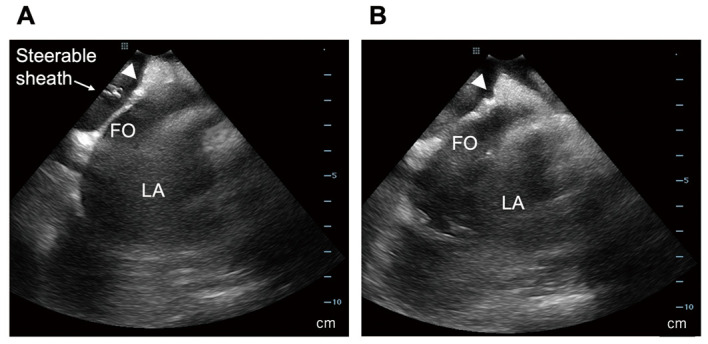

Background: Atrial biopsy is technically challenging owing to the atria's thin walls and relatively thick endocardium. This study assessed the feasibility and safety of echocardiography-guided atrial biopsy in a consecutive cohort of 1,000 patients who underwent catheter ablation for atrial tachyarrhythmias or percutaneous left atrial (LA) appendage occlusion.

Methods and results: Atrial biopsy was performed at the limbus of the fossa ovalis through the femoral vein using a 5.5-Fr (n=233) or a 7.0-Fr (n=767) bioptome under intracardiac (n=963) or transesophageal (n=37) echocardiography guidance, alongside fluoroscopy. For histological analysis, 5 tissue samples were collected from the same site. Biopsy was successfully completed in 996 (99.6%) patients. Patients were divided based on histological depth into Group A (biopsy beyond the endocardium; n=885) and Group B (endocardial-only biopsy; n=111). Multivariable logistic regression identified larger LA volume, use of a 5.5-Fr bioptome, and amyloid deposition as independent predictors of Group B (P=0.009, P<0.001, and P=0.001, respectively). Moreover, biopsy-related complications were unrecorded.